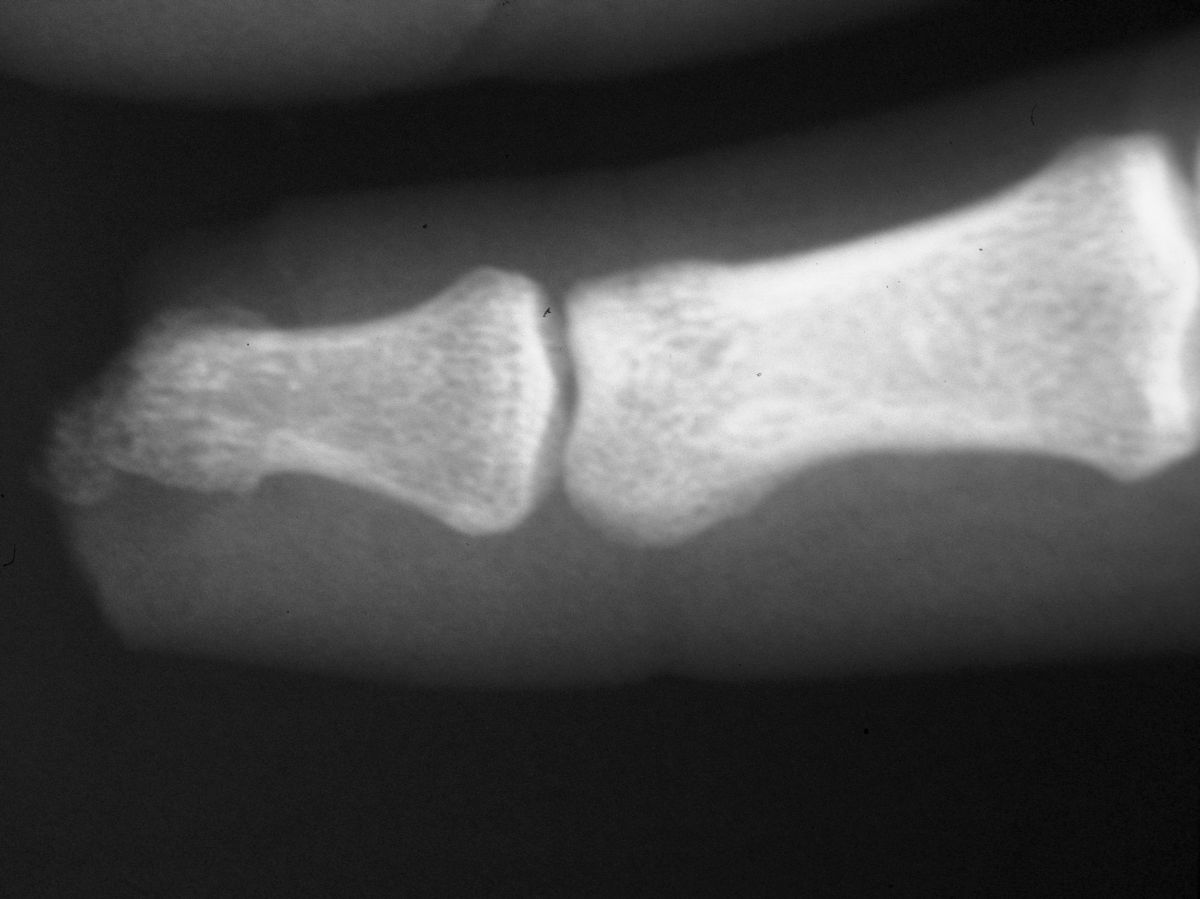

| Distal phalanx

fracture stabilization. Pins were placed to protrude

proximally in anticipation of flap cover. |